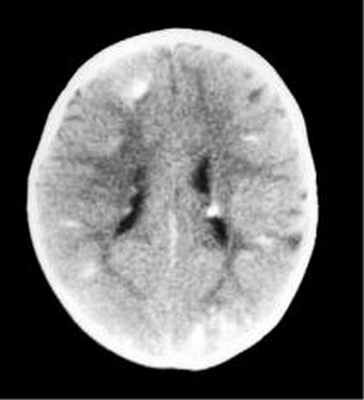

Наиболее типичными нарушениями в головном мозге являются корковые туберсы и субэпендимарные узлы. Туберсы могут быть как единичными, так и множественными, располагаются в виде выступов над единичной или прилегающими бороздами коры, расширяя их. Субэпендимарные узлы локализуются в стенках боковых желудочков и, реже, в стенках III и IV желудочков мозга. У новорожденных субэпендимарные узлы редко бывают кальцифицированными. По мере роста ребенка наблюдается постепенное отложение кальция в субэпендимарных узлах.

Субэпендимарные узлы в 10% случаев трансформируются в гиганто-клеточную астроцитому, которые манифестируют обычно между 5 и 10 годами жизни, имеют тенденцию к росту и локализуются у отверстия Монро

Субэпендимарные кальцификаты и корковые туберсы на КТ головного мозга ребенка с туберозным склерозом

КТ головного мозга при туберозном склерозе. Видны кальцинированные субэпендимальные узелки в стенках боковых желудочков.